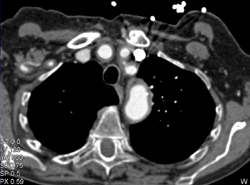

Nice IVC Opacification of Renal Veins